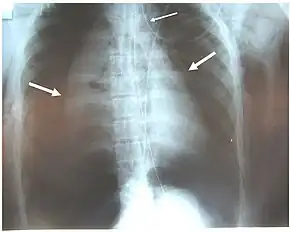

Chest x-ray is the initial imaging technique used to diagnose TBI.[17] The film may not have any signs in an otherwise asymptomatic patient.[15] Indications of TBI seen on radiographs include deformity in the trachea or a defect in the tracheal wall.[17] Radiography may also show cervical emphysema, air in the tissues of the neck.[2] X-rays may also show accompanying injuries and signs such as fractures and subcutaneous emphysema.[2] If subcutaneous emphysema occurs and the hyoid bone appears in an X-ray to be sitting unusually high in the throat, it may be an indication that the trachea has been severed.[4] TBI is also suspected if an endotracheal tube appears in an X-ray to be out of place, or if its cuff appears to be more full than normal or to protrude through a tear in the airway.[17] If a bronchus is torn all the way around, the lung may collapse outward toward the chest wall (rather than inward, as it usually does in pneumothorax) because it loses the attachment to the bronchus which normally holds it toward the center.[6] In a person lying face-up, the lung collapses toward the diaphragm and the back.[23] This sign, described in 1969, is called fallen lung sign and is pathognomonic of TBI (that is, it is diagnostic for TBI because it does not occur in other conditions); however it occurs only rarely.[6] In as many as one in five cases, people with blunt trauma and TBI have no signs of the injury on chest X-ray.[23] CT scanning detects over 90% of TBI resulting from blunt trauma,[3] but neither X-ray nor CT are a replacement for bronchoscopy.[6]